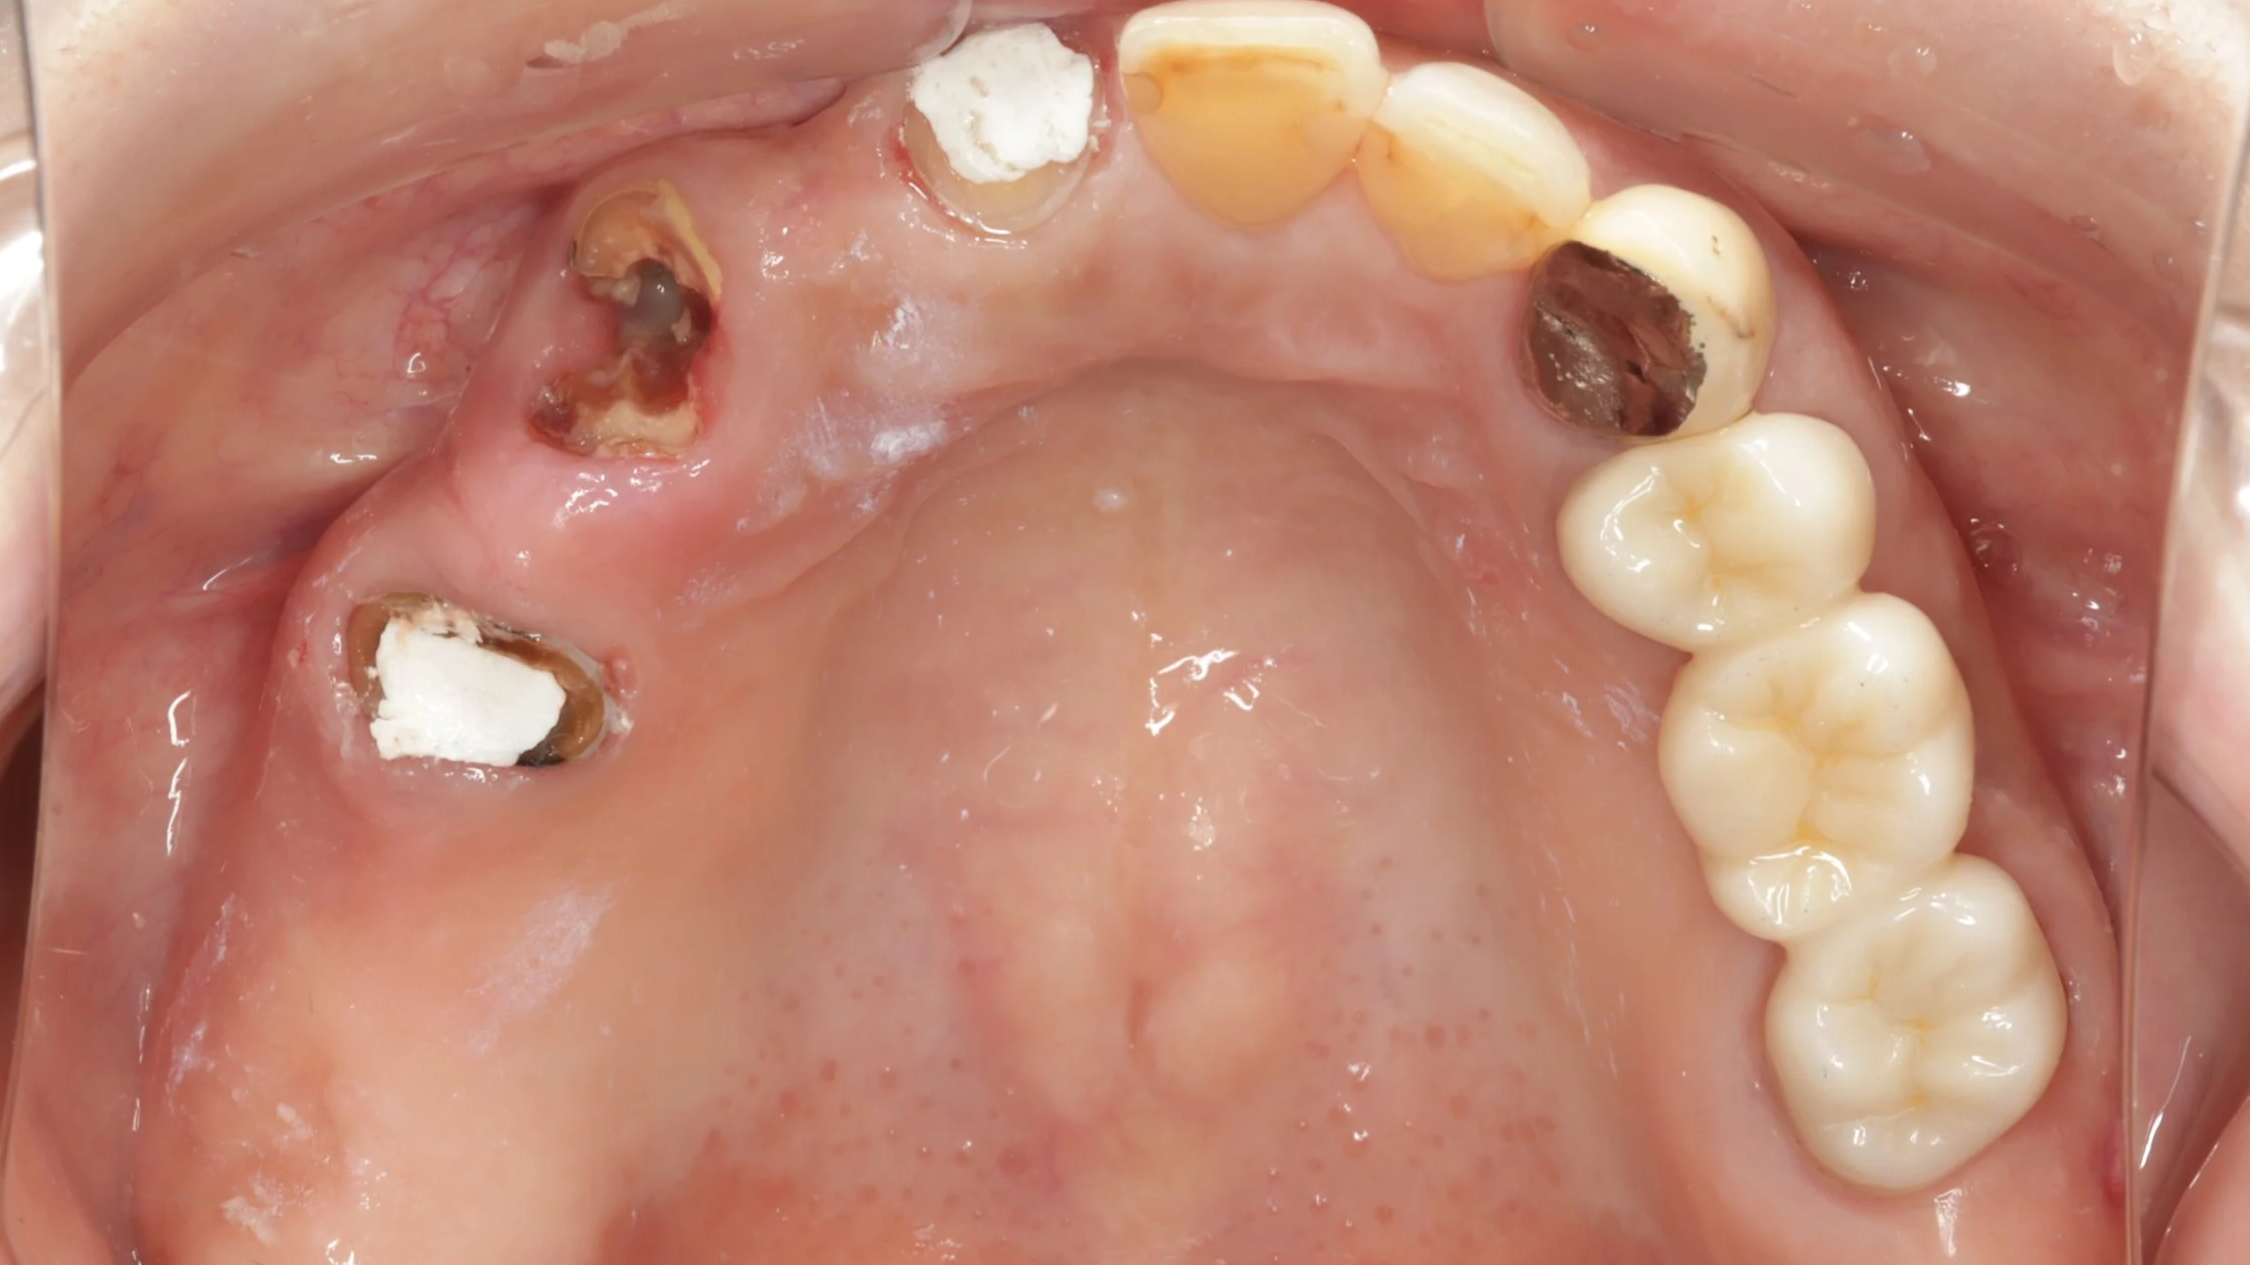

初診時

上の前歯の根はすでに割れており抜歯の必要がありました。抜歯了承後、入れ歯のためのデジタルでの型取りを行いました。

大きなむし歯もある状態でしたがまずは、入れ歯を早期に装着し、入れ歯の調整をしつつ、歯の治療することとしました。